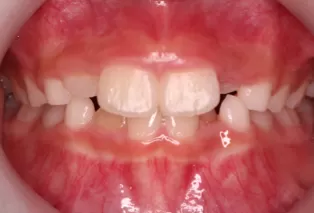

Photos intra-orales